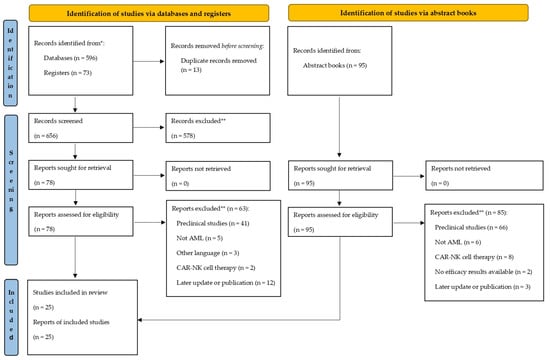

Open AccessSystematic Review

CAR-T Cell Therapy for Acute Myeloid Leukemia: Where Do We Stand Now?

by

Pilar Lloret-Madrid, Pedro Chorão, Manuel Guerreiro and Pau Montesinos

Curr. Oncol. 2025, 32(6), 322; https://doi.org/10.3390/curroncol32060322 - 30 May 2025

Background: Patients with refractory and relapsed acute myeloid leukemia (R/R AML) face a dismal prognosis. CAR-T therapy has emerged as a potential treatment option. This study assesses the available clinical evidence on CAR-T in R/R AML, focusing on safety and efficacy outcomes.

[...] Read more.

Background: Patients with refractory and relapsed acute myeloid leukemia (R/R AML) face a dismal prognosis. CAR-T therapy has emerged as a potential treatment option. This study assesses the available clinical evidence on CAR-T in R/R AML, focusing on safety and efficacy outcomes. Methods: We included studies on CAR-T therapy for R/R AML published from June 2014 to January 2025. Data on patient and disease characteristics, CAR-T constructs, response rates, post-CAR-T allogeneic HSCT (allo-HSCT), and safety outcomes were analyzed. Results: Twenty-five CAR-T clinical trials involving 296 patients were identified. The most frequently targeted antigens were CD33, CD123, and CLL-1, while CD7, CD19, NKG2D, and CD38 were also explored. Responses were heterogeneous and often short-lived when not consolidated with allo-HSCT. Cytokine release syndrome and neurotoxicity were generally low grade and manageable. Prolonged and severe myelosuppression was a frequent limiting toxicity, often requiring allo-HSCT to restore hematopoiesis. Disease progression was the leading cause of death, followed by infections. Conclusions: CAR-T cell therapy may represent a feasible therapeutic strategy, particularly as bridging to allo-HSCT to mitigate myelotoxicity and improve long-term outcomes. Nevertheless, it remains in the early stages of development and faces significant efficacy and safety challenges that must be addressed in future trials to enable the expansion of this promising therapeutic approach for a population with high unmet medical needs.

Full article

(This article belongs to the Special Issue Future Perspectives for Treatment and Diagnosis of Acute Myeloid Leukemia (AML))

►▼

Show Figures

Figure 1